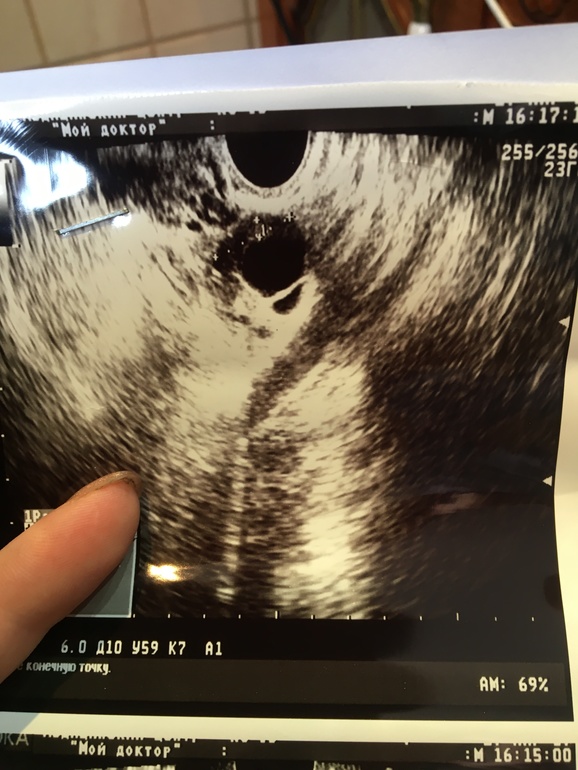

как понять ? врач сказала это Жт вот вот произошла овуляция, жидкость видите вокруг ?

У меня по другому выглядело жт,а вот фолик начавший лопаться именно так выглядел